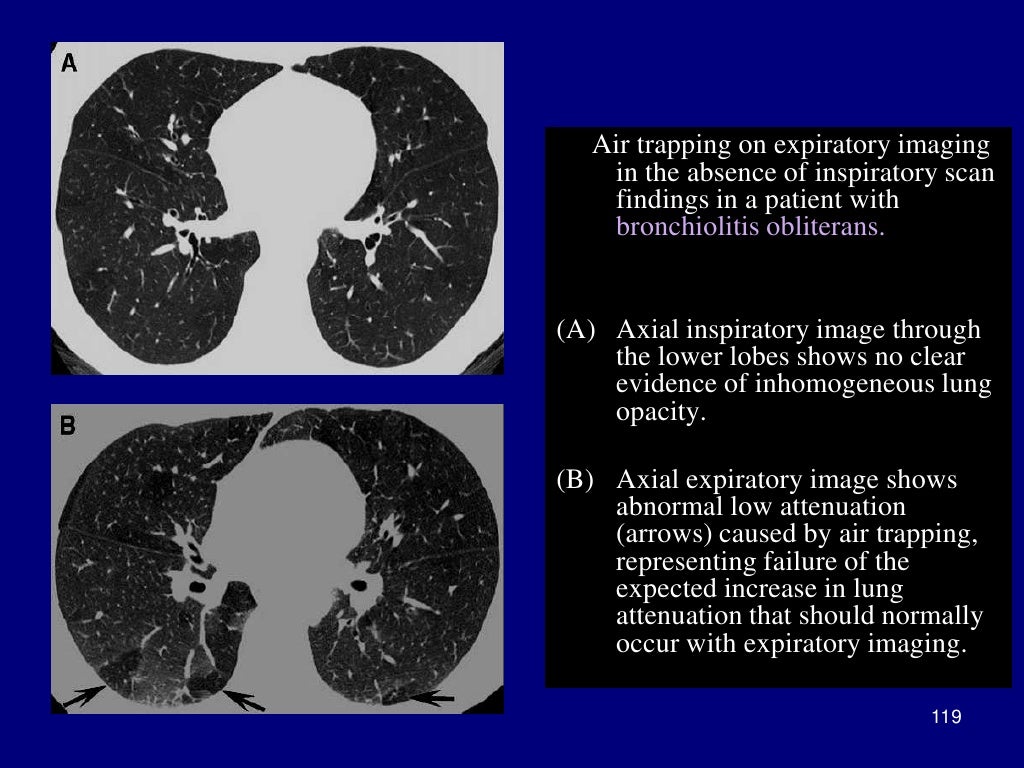

From www.slideserve.com